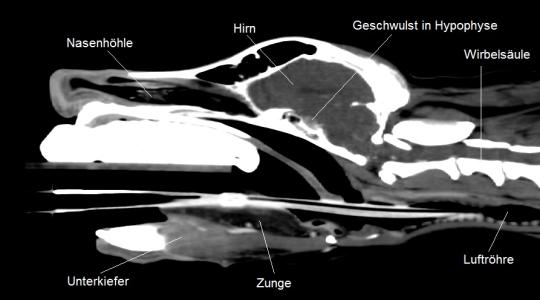

Weitere Blutuntersuchungen am Unispital unterstützen den Verdacht eines hypophysären Cushingsyndroms; ein abschliessendes Computertomogramm bestätigt dann, dass sich in der Hirnanhangsdrüse ein kleiner Geschwulst gebildet hat, welcher offensichtlich hormonell aktiv ist.

Computertomogramm des Kopfes (Längsschnitt) - Bildmaterial: Tierspital Zürich, Abteilung für Bildgebende Diagnostik und Abteilung Radio-Onkologie